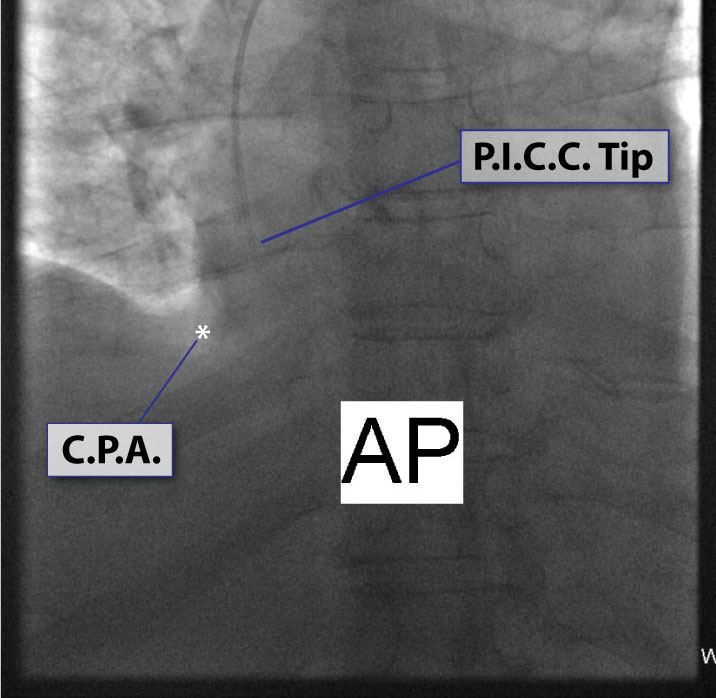

3. Chest x-ray rotation tissues: Not infrequently, the chest x-ray will be rotated causing the right cardiac margin to deviate from its normal AP appearance. In such situations, depending on the degree of rotation, an estimation of the SWEET SPOT™ is all that may be possible. In such circumstances, the right cardiophrenic angle is the most reliable anatomic landmark. Since the right atrium is immediately cephalad to a normally positioned right cardiophrenic angle, a reliable estimation of acceptable catheter tip location is still possible. The height, and consequently the width of the rectangular Sweet Spot™ box will be less exact and therefore a relatively short catheter tip position may require a non- rotated chest x-ray to confirm an acceptable location. Aim for the right atrium. See Figs. T.1, T.2, and T.3.

8. Even on normal frontal chest x-rays, there can be significant variation in the appearance of the cardiomediastinal silhouette which can result in slight subjectivity in the exact location of the margins of the SWEET SPOT™. The closer the catheter tip is to the cavoatrial junction, the less this matters.